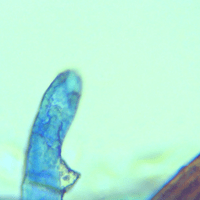

Around 240 million people worldwide have it and more than 200,000 deaths per year are a result of schistosomiasis.- Schistosomiasis is now being found in first world countries such as the US and UK from persons with no travel history to endemic countries. - How is Schistosomiasis transmitted? - Individuals get infected when they come into contact with fresh water contaminated with the schistosome parasite. Fresh water becomes contaminated with the parasite when individuals infected with schistosomiasis urinate or defecate in the water, releasing the parasite’s eggs, which later hatch.The parasite larvae then develop and multiply inside specific types of freshwater snails, before re-entering the water. Then it can survive for up to 48 hours in the water as it swims around looking for a human host to infect. - Recent developments have revealed that Schistosomiasis can be transmitted sexually between partners. Testing is underway and results are coming in of both partners being infected with Schistosomiasis. - How does it affect you? - When the schistosome parasite finds a host in the water, it burrows into your skin where it typically will leave red bumps or a swimmers like rash. After this it makes its way to the capillaries entering into the circulatory system stopping first in the lungs. After that phase the parasite changes into a small worm like parasite and starts to move to your liver. Once in your liver the parasite goes through its final phase and becomes an adult worm where it moves again settling into its residence either the blood vessels located around your bladder (Haematobium)or the blood vessels around your intestines (Mansoni). Once there is when the real damage starts to take place, eggs. Now that the worm is in its adult form it finds a mate and they begin to produce thousands of eggs a day. The eggs migrate through the attaching tissue into either the bladder or intestines to be expelled by the human host and hence perpetuate the cycle all over again. This is where the true damage of the disease takes place as the eggs irritate the linings and cause inflammation. Some of the eggs will be trapped due to your bodies natural defenses and cysts will form that later can develop into cancer. Frequent urination and or frequent deification of loose or floating stool is a strong symptom of schistosomiasis. Why floating? Floating is what the parasites have evolved to do as human host are more likely accessible at the surface of fresh waters. - In STD transmissions the first signs of it show up as an UTI with frequent urination and malaise. If left untreated the more severe and associated schistosomiasis symptoms appear. - If you suffer from IC (Interstitial cystitis) or painful bladder syndrome there is a good chance that it is Schistosomiasis. - Symptoms of Schistosomiasis - A red rash or bumps on the skin from being exposed to infected water (usually visible in 12 hours after exposure)

- Avian Schistosomiasis - Trichobilharzia - The bird schistosomes are a group of blood flukes (Platyhelminthes, Digenea). They contain the largest clade of the family Schistosomatidae that includes ten genera: Dendritobilharzia, Gigantobilharzia, Allobilharzia, Austrobilharzia, Anserobilharzia, Trichobilharzia, Bilharziella, Macrobilharzia, Ornithobilharzia and Jilinobilharzia. In the two-host life cycle (fresh water snails as intermediate hosts and aquatic birds as definitive hosts), they develop as adults with in venous and arterial vessels or nasal tissue of their bird host. Bird schistosomes of the genus Trichobilharzia are categorized as nasal and visceral groups depending on their target tissue within the final hosts (Horák et al., 2002; Brant et al., 2006). Cercariae of the bird schistosomes released from intermediate hosts are recognized as the great causative agent of human cercarial dermatitis (HCD) or Swimmer's itch which is considered an emerging disease in various parts of the World (de Gentile et al., 1996). Experiments have demonstrated that avian schistosomes can migrate and partly develop in other bodies of their non-specific mammalian hosts, causing serious health risks. Larvae of different visceral avian schistosome have been detected in the lungs of experimentally infected monkeys and rodents (Horák et al., 2002), and foot paralysis has been seen in mice infected with the neurotropic species Trichobilharzia regenti(Horák et al., 1999; Hrádková and Horák, 1999). Therefore, as a result of these experiments, It is thus considered conceivable that avian schistosomes may be responsible for some nervous or pulmonary symptoms in humans... - https://www.sciencedirect.com/science/article/pii/S2405673120300118